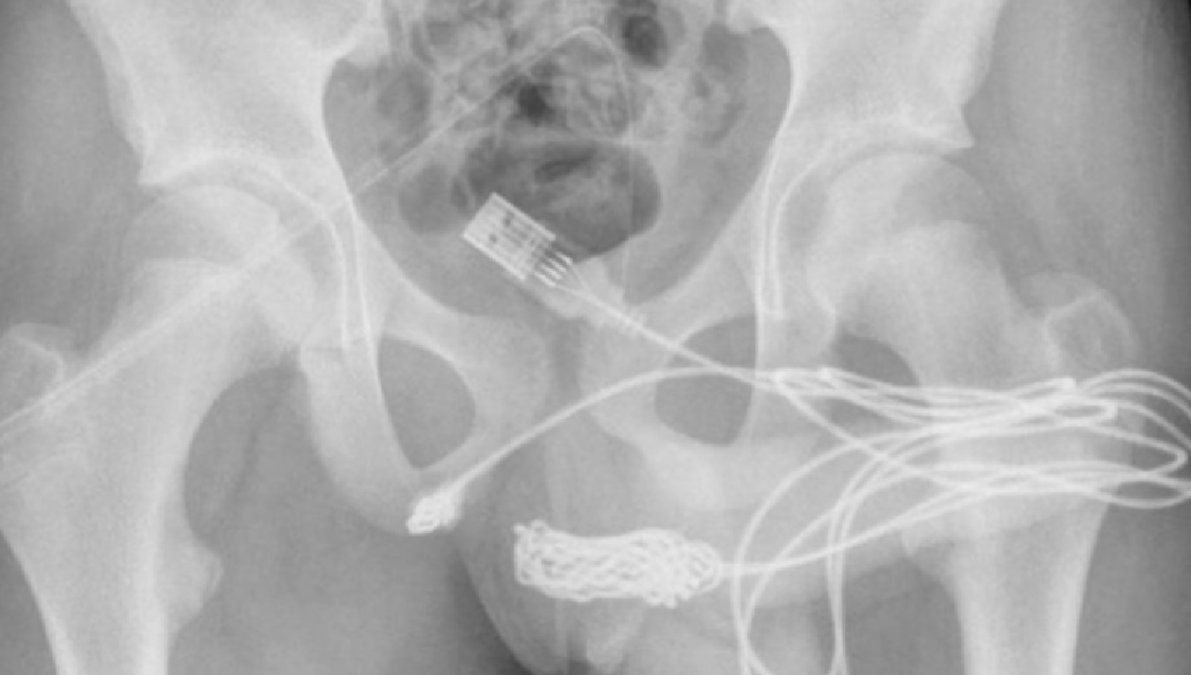

Las radiografías posteriores revelaron que había un verdadero enredo de cable dentro del adolescente. Por ello, los cirujanos hicieron una incisión en la región entre sus genitales y el ano para sacarlo. Primero tiraron del extremo enrollado a través del agujero, cortándolo libre del resto del cable antes de quitar los trozos restantes, literalmente tirando del enchufe.